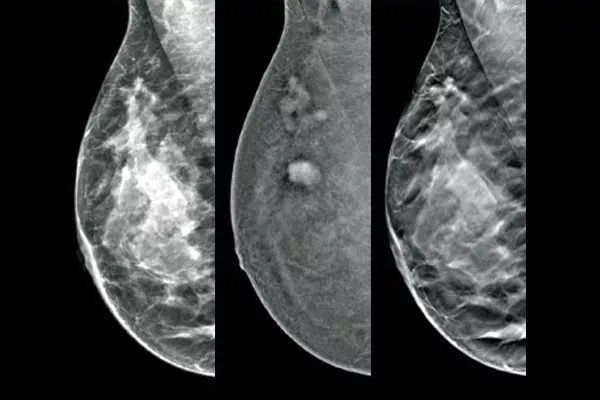

The Affirm® Contrast Biopsy Solution enables the targeting and acquisition of breast tissue in lesions identified during contrast-enhanced mammography (CEM). Designed to maximise workflow efficiency while improving the patient experience, the complete Contrast Biopsy solution simplifies the breast biopsy process,* even for challenging procedures.

Target and biopsy lesions identified with 2D contrast-enhanced mammography through a stereotactic-based procedure, with a comparable diagnostic performance to a breast MRI procedure.1,2 Compare post-marker images in the same modality as the initial diagnostic contrast exam.

Affirm Contrast Biopsy software allows you to biopsy lesions identified during the I-View® contrast-enhanced 2D mammogram. By leveraging the ability to provide 2D, contrast-enhanced, and tomosynthesis images under one compression,4 The Affirm Upright Breast Biopsy Guidance System enables a quick transition from screening to biopsy, leveraging the same proven imaging chain5 as the mammography system to improve 3D™ visualisation of suspicious lesions.**

An Efficient & Cost-Effective Alternative to MRI

Functional imaging, using CEM, compares favourably to breast MRI with similar sensitivity, higher specificity, and higher positive predictive value.7,8 In addition, CEM provides a cost-effective diagnostic imaging alternative9 compared to MRI, with a shorter procedural time.7,10